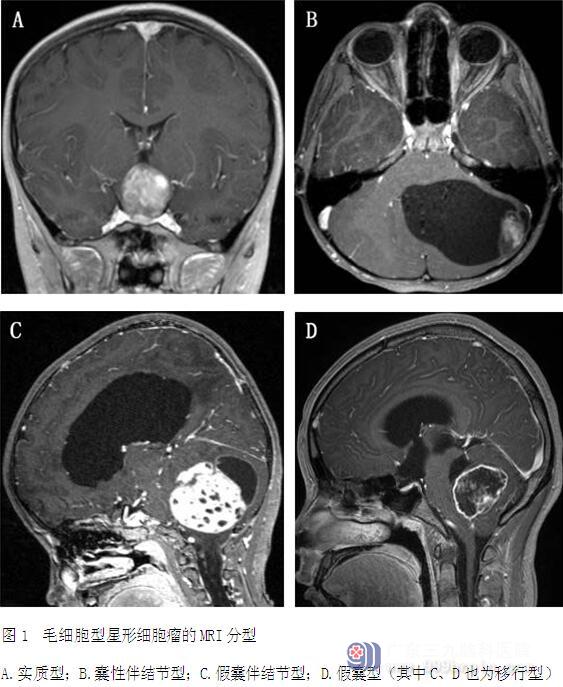

2.影像学资料:所有患者术前和术后均行头颅MRI检查。根据PA的影像学特点,可分为5种类型 (图1):(1)实质型,肿瘤呈基本均匀性团块状强化;(2)囊性伴壁结节型,仅壁结节强化,瘤壁无强化,该型囊壁由反应性增生的胶质成分构成,壁内无肿瘤细胞;(3)假囊性伴壁结节型,增强后囊壁和壁结节强化;(4)假囊型,增强后肿瘤呈厚薄不均的环状强化;(5)移行型,由小脑半球向前突出小脑轮廓外并累及脑桥。其中假囊性伴壁结节型和假囊型均由实质型发生坏死、囊变而来。本组实质型26例,囊性伴壁结节型25例,假囊性伴壁结节型18例,假囊型18例,移行型5例。